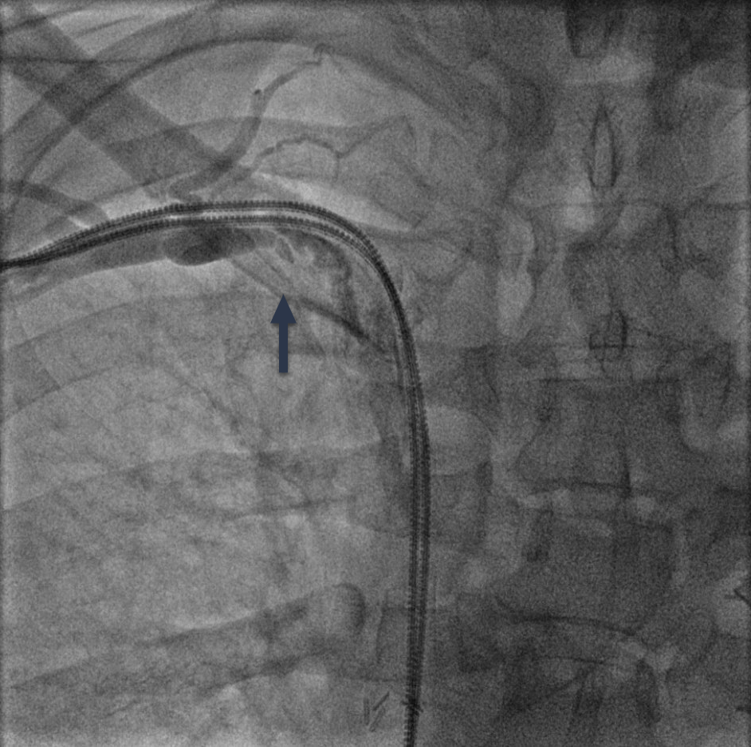

RHC procedure. Arm venous access was obtained with ultrasound guidance in all cases. After successful ‘radial’ sheath insertion, a 5-French (Fr) or 6-Fr balloon flotation right heart catheter was advanced (either by itself or over a 0.014-inch coronary guidewire based on operator preference) through the sheath and then into the pulmonary artery (PA). If resistance to catheter passage was encountered, a venogram (Figures 1A, 2A, and 3A) was performed using diluted contrast (50% saline) to determine the venous anatomy, the location, and the extent of stenosis, and to guide further wire/catheter advancement. In some cases, using different guidewires or catheters (eg, downsizing a 6 Fr to a 5 Fr) allowed RHC success. When a 0.014-inch wire was advanced into the superior vena cava (SVC) and the passage of a balloon-tip right heart catheter over the wire was unsuccessful due to a stenosis and/or pacemaker/ICD wires, a coronary balloon or 0.014-inch compatible peripheral balloon was then advanced over the wire and dilatation of the stenosis was performed (Figures 1B, 2B, and 3B). In some cases, a single balloon dilatation allowed passage of the RHC catheter. In others, a progressive increase in balloon diameters was needed. At the end of the procedure, the venous sheath was withdrawn, and manual compression was applied to the puncture site until hemostasis was attained.

We were able to pass a guidewire through all stenoses. A coronary or peripheral balloon catheter was then passed over the guidewire, and dilatation was performed (Figures 1B, 2B, and 3B). Coronary angioplasty balloons were utilized in 8 (44.4%), peripheral balloons in 7 (38.9%), and both peripheral and coronary balloons in 3 patients (16.7%). The balloons used were predominantly non-compliant (83.3%). Eleven patients (61.1%) required only a single balloon for successful venoplasty, while 7 patients (38.9%) had at least 2 balloons used, upsizing from the previously used balloon. The balloons' median diameter and length were 4 mm (range, 3-4 mm) and 60 mm (range, 20-200 mm), respectively. The median highest inflation pressure used was 14 atm (range, 8-18). After SVS dilatation, we performed successful RHC in 100% of the cases with a catheter passed into the PA. The average length of the procedure for successful RHC was 35.2 ± 15.5 minutes. There were no complications at the end of the procedure in any of our patients.